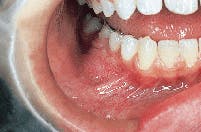

The patient`s vital signs were all found to be within normal limits. Examination of the head and neck region revealed no enlarged or palpable lymph nodes. Intraoral examination revealed a localized bony hard swelling buccal to teeth #28, 29, and 30 (see photo). The mass measured approximately 2.5 cm in diameter. Further examination of the oral tissues revealed no other lesions present.